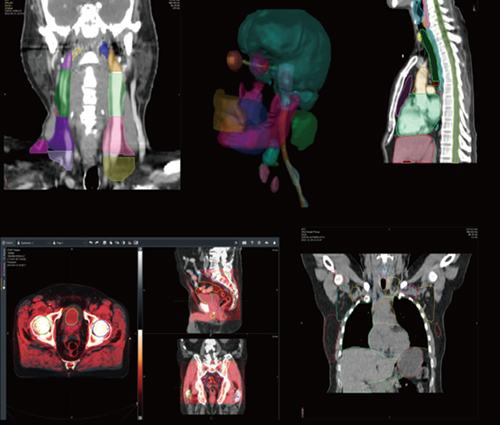

Elekta ONE|Planningの画面例

GPUの採用などにより,治療計画に要する時間の大幅な短縮を実現している。